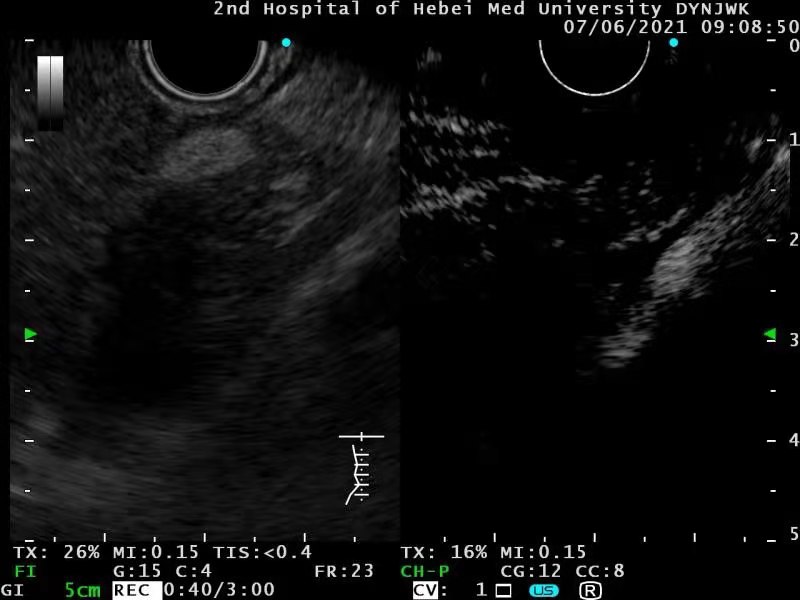

EUS还见到其余两个图像

2、胰颈部高回声

弹性成像

血流